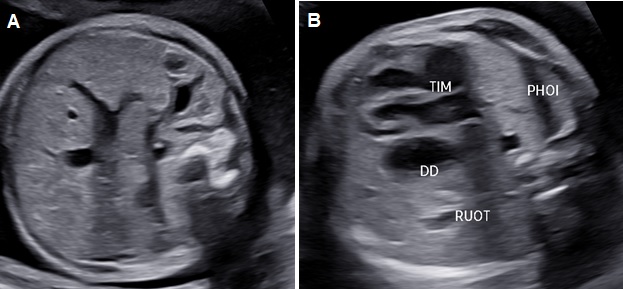

Hình 2. Thoát vị hoành trái. A: Mặt cắt ngang bụng không thấy dạ dày. B: Mặt cắt ngang 4 buồng tim có hình ảnh dạ dày (DD) và ruột đẩy sát tim qua sát thành ngực phải; phổi phải bị chèn ép.

Thoát vị hoành trái: Ở mặt cắt ngang 4 buồng tim có khối phản âm không đồng nhất ở trong lồng ngực trái có thể là dạ dày chứa dịch bên trong (+/-) ruột, gan. Trung thất và tim bị đẩy lệch qua bên phải (Dextroposition). Ở mặt cắt ngang bụng không thấy dạ dày nếu đã bị thoát vị lên lồng ngực.

Thoát vị hoành phải nếu chỉ đơn thuần gan lên có thể khó nhận diện vì phản âm của gan tương tự phổi trên siêu siêu âm thang xám. Hình ảnh đường mật, túi mật là đặc trưng giúp nhận diện gan. Doppler màu có gía trị vì giúp nhận diện các tĩnh mạch gan. Dấu hiệu gián tiếp có thể thấy là hình ảnh trục tim bị lệch.